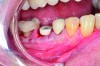

Case Presentation

Fig 1. Immediate implant placement with a PEEK healing abutment to contour soft tissue, mandibular right first molar.

Figure 1